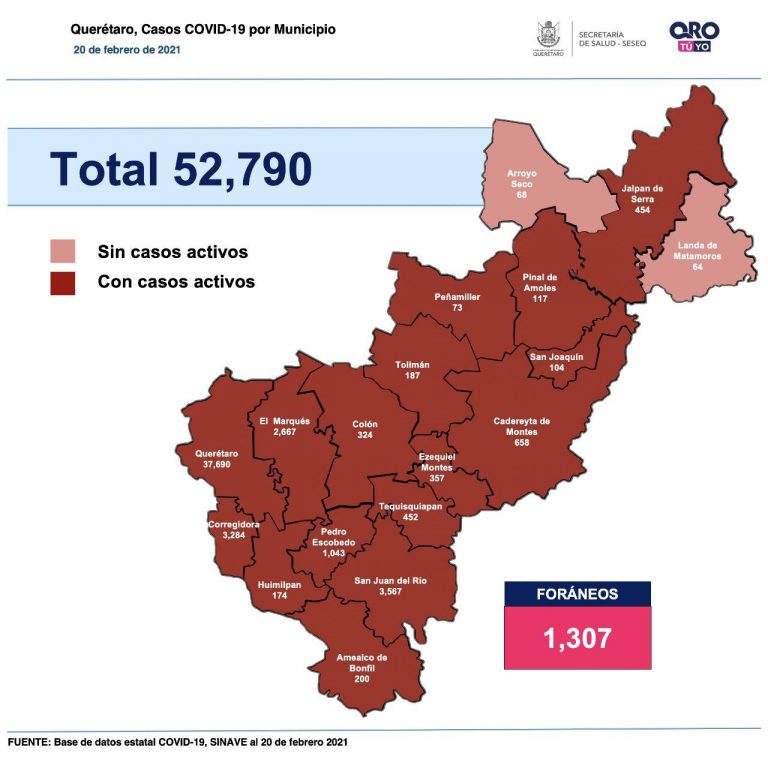

Se suman 227 casos de Covid-19 en Querétaro